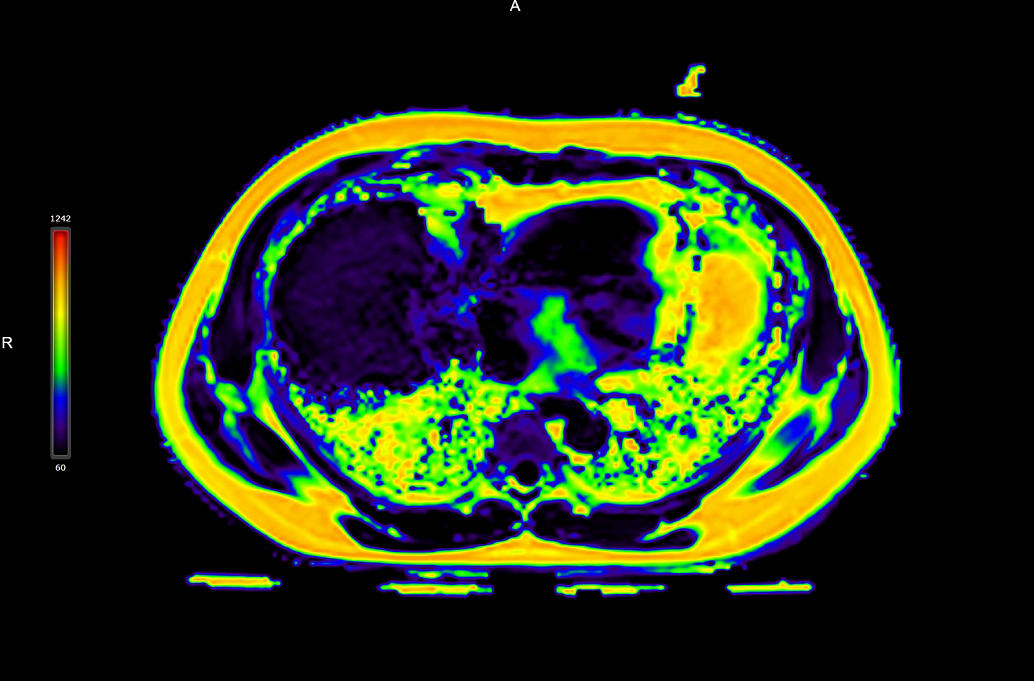

磁共振全面多病种定量临床应用